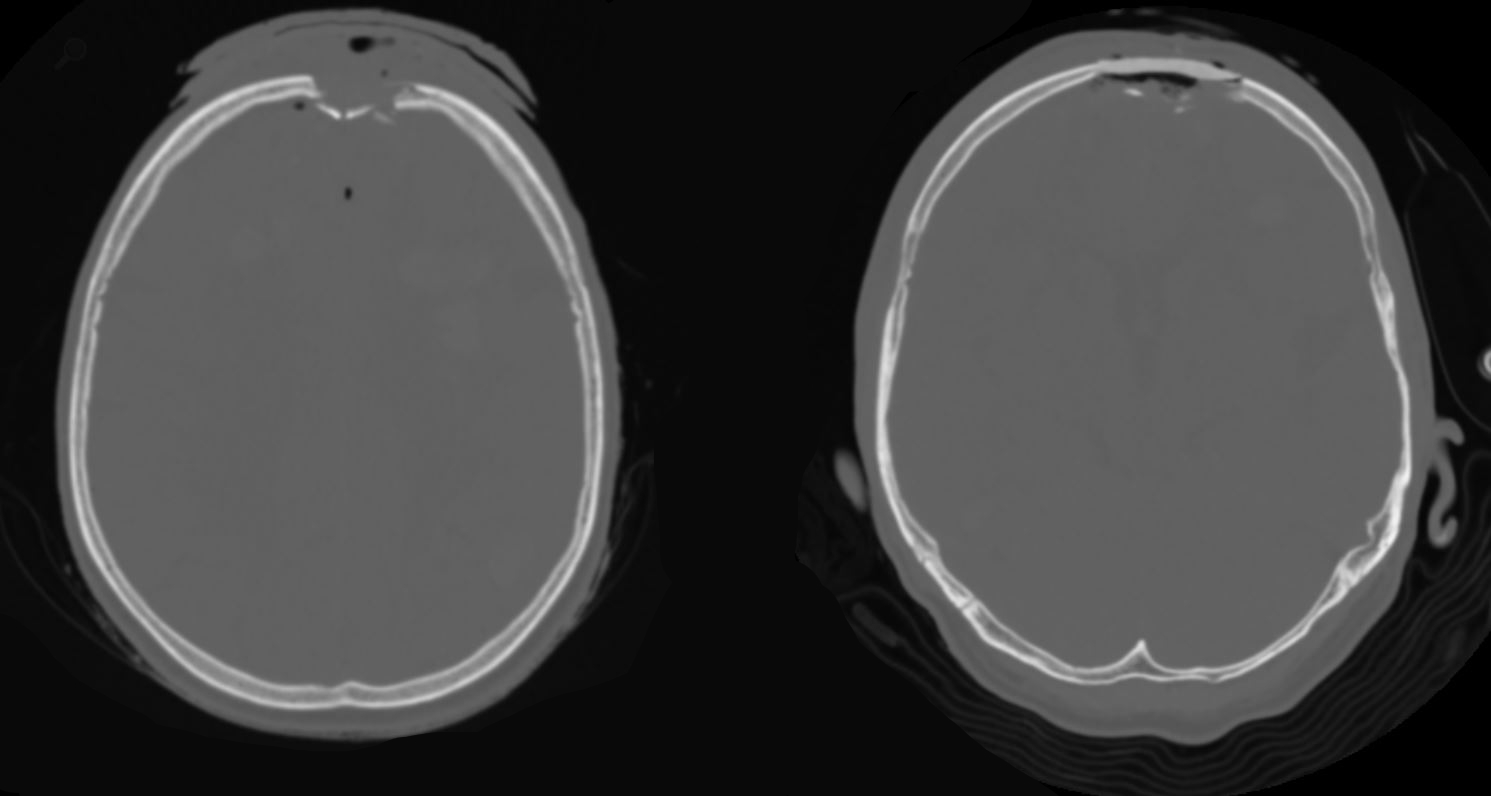

Impressionsfraktur CT

Darstellung einer Impressionsfraktur frontal rechts im Rahmen eines Autounfalls.